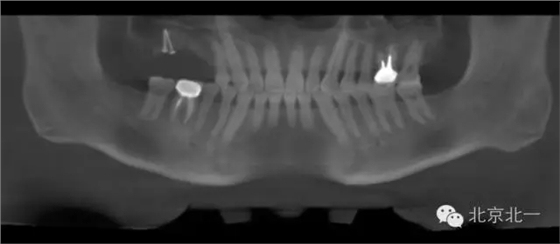

圖十八:手術前CBCT

圖十九:手術后當天CBCT

圖二十-二十二:ONLAY植骨半年后

圖二十三:種植后當天全景片。